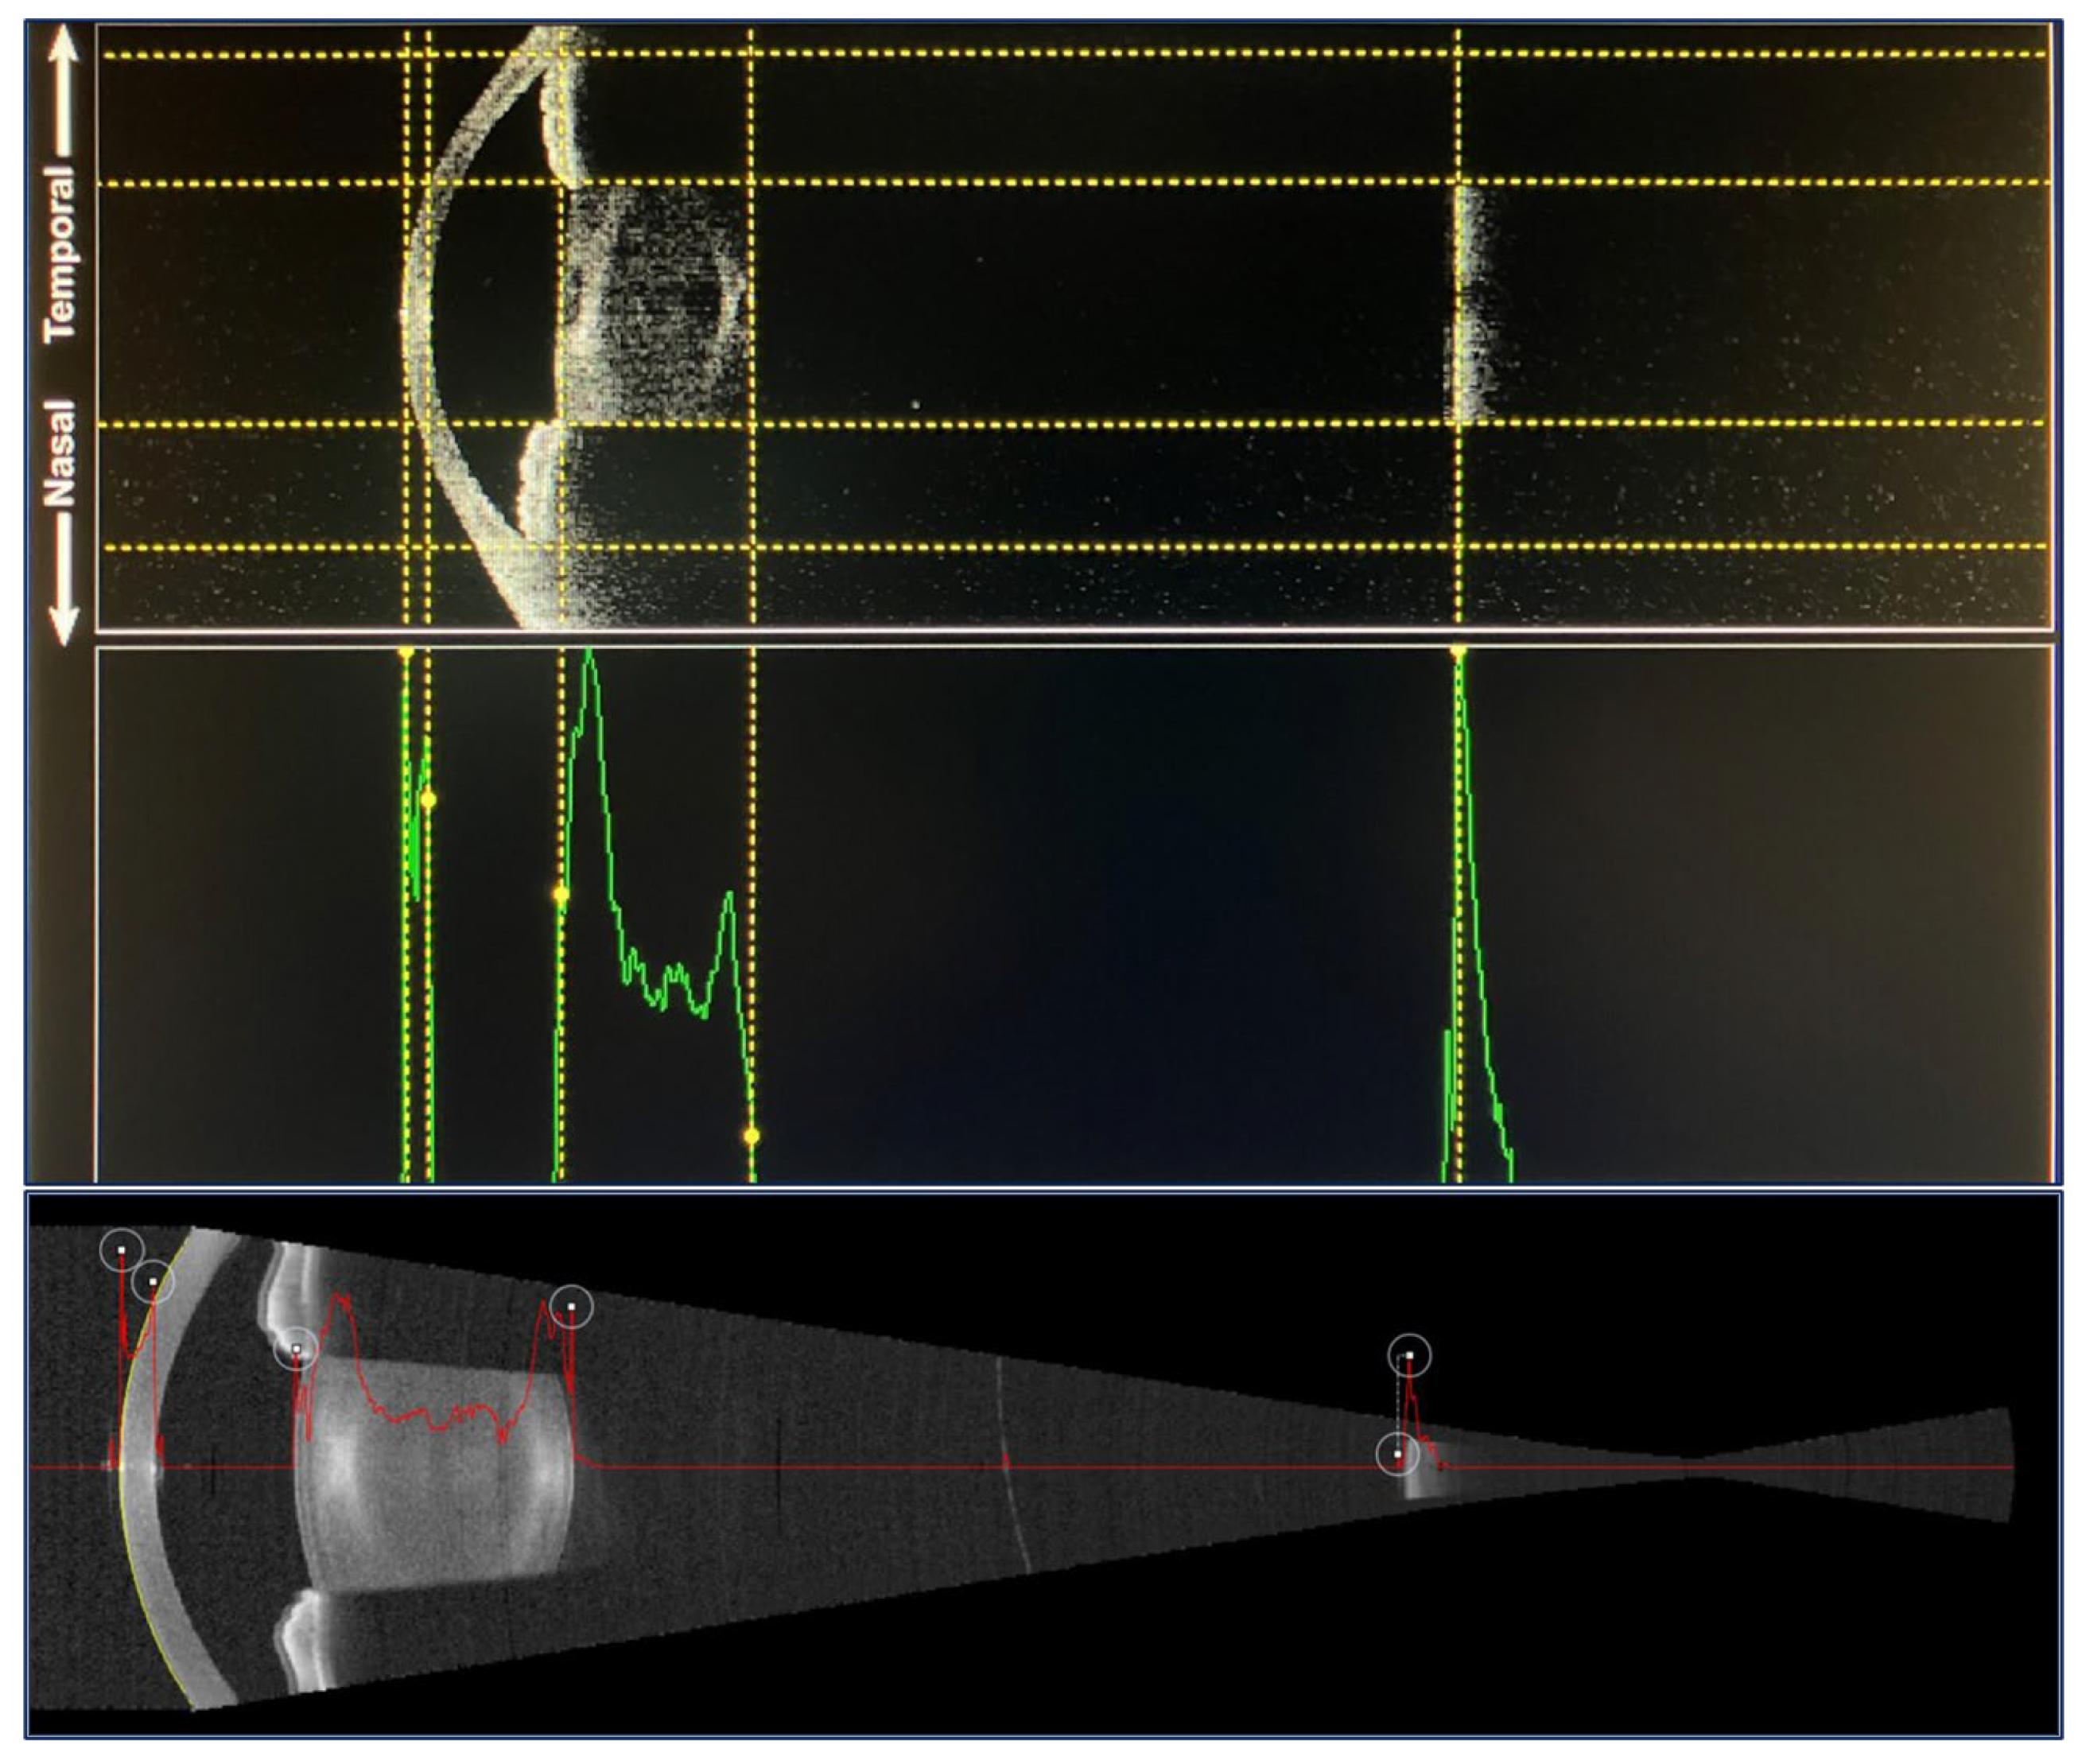

| Characteristics | Argos® | Eyestar 900® |

|---|---|---|

| Manufacturer | Alcon Healthcare | Haag-Streit |

| Method | SS-OCT | SS-OCT |

| Center wavelength | 1060 nm | 1060 nm |

| Scan speed | 3000 A-scans/s | 30,000 A-scans/s |

| B-scan axial resolution | 50 µm | N/R |

| Scan depth range | 50 mm | 14 to 38 mm |

| Last generation formulas available | Yes | Yes |

| AL measurement approach | Sum of segments | Group refractive index |

| Other | Enhanced Retina Visualization, integration with other devices | Quantification of lens tilting, vision simulator |